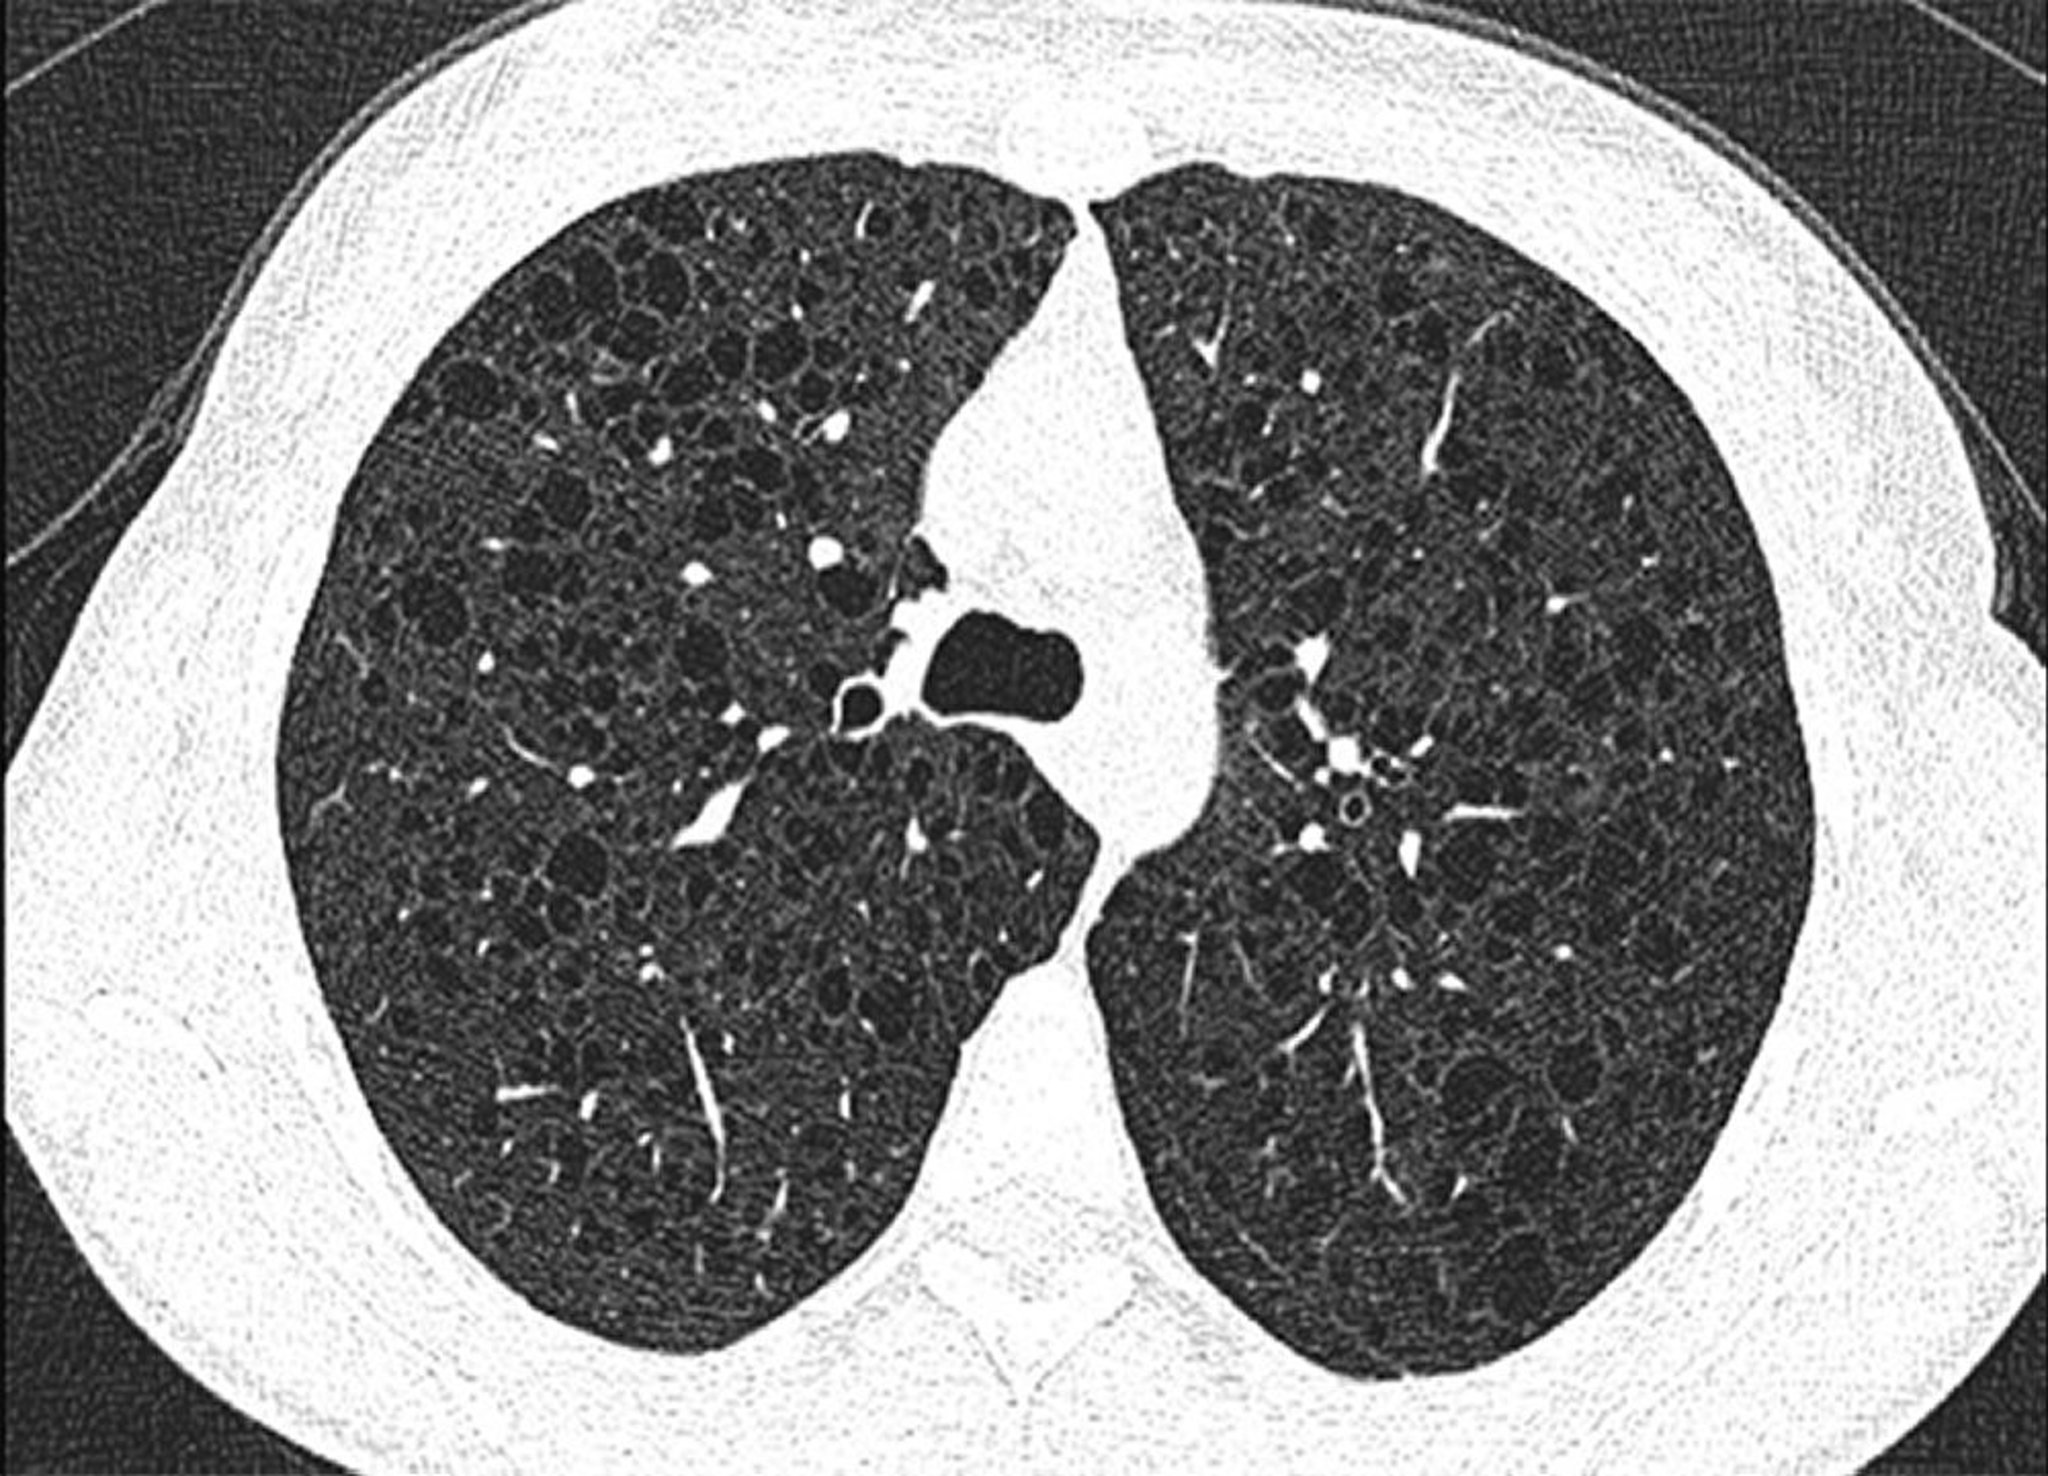

This image shows diffuse cysts in both lungs in a patient with lymphangioleiomyomatosis.

Image courtesy of Joyce Lee, MD, MAS.